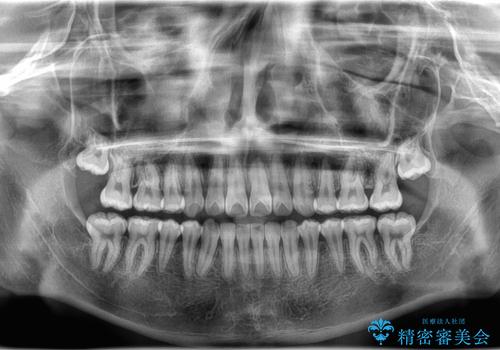

八重歯・歯並びのデコボコとディープバイトを改善した抜歯ワイヤー矯正症例

- 八重歯と咬み合わせを治したいを主訴にご来院された患者様です。

矯正の精密検査の結果上顎左右4番の計2本を抜歯し、審美性に配慮したワイヤー矯正装置(審美装置)を用いて治療を行いました。

八重歯などの歯列のデコボコが綺麗に改善され、患者様にも大変喜んでいただけました。また、咬み合わせが深い「ディープバイト」も併せて改善し、見た目だけでなく機能面でもバランスの取れた咬合を獲得しています。